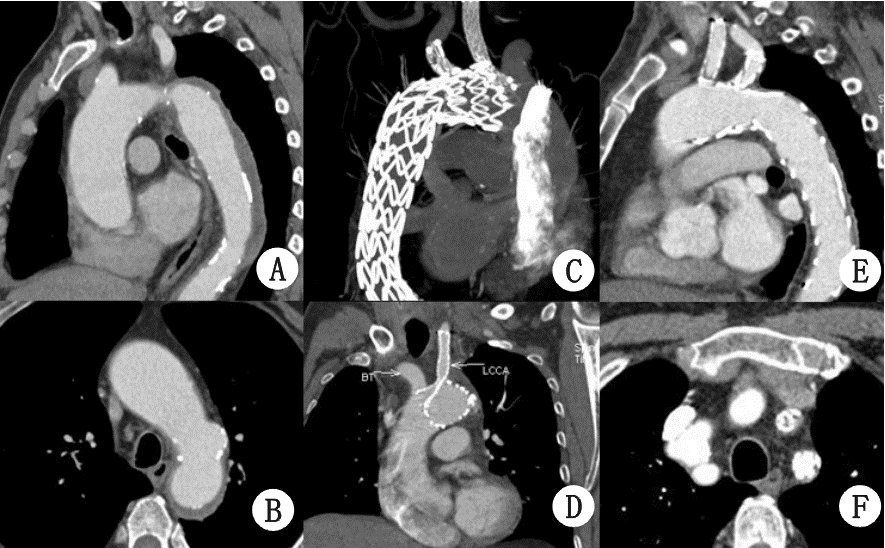

| A:对照组;B:ALI组 图 2 病例2,A-B:术前CTA可见壁间血肿和穿透性溃疡;C-D:术后6个月随访CTA,无内漏,血管重构良好,单分支支架通畅,烟囱支架被主体支架压迫狭窄;E-F:术后12个月随访CTA,单分支支架通畅,烟囱支架被压迫出血栓形成闭塞 |

所有患者均一期手术成功,支架主体定位精确,烟囱支架位置形态好,术后造影无明显狭窄。未发生死亡、脑梗死、肾功能不全等围手术期严重并发症,术后造影穿透性溃疡封闭良好,夹层近端破口被封堵,未见明显内漏。随访期间,无患者死亡。随访12~18个月,随访CTA显示:支架形态良好,无明显移位,主动脉壁间血肿被吸收,术后6个月随访1例左锁骨下动脉分支支架在左锁骨下动脉开口处狭窄约40%,12个月随访时无明显改变(图 1 C箭头),进一步随访中;其余2例分支支架通畅无狭窄扭曲,3例患者均未见明显内漏(图 1-3 )。1例左颈总烟囱支架术后6个月随访时,被主体支架压迫烟囱支架使颈总开口处狭窄(图 2C,D),术后12个月随访时在颈总动脉开口处血栓形成闭塞(图 2E,F),无头晕、脑梗等颅内缺血表现,未做特殊处理,继续随访中。